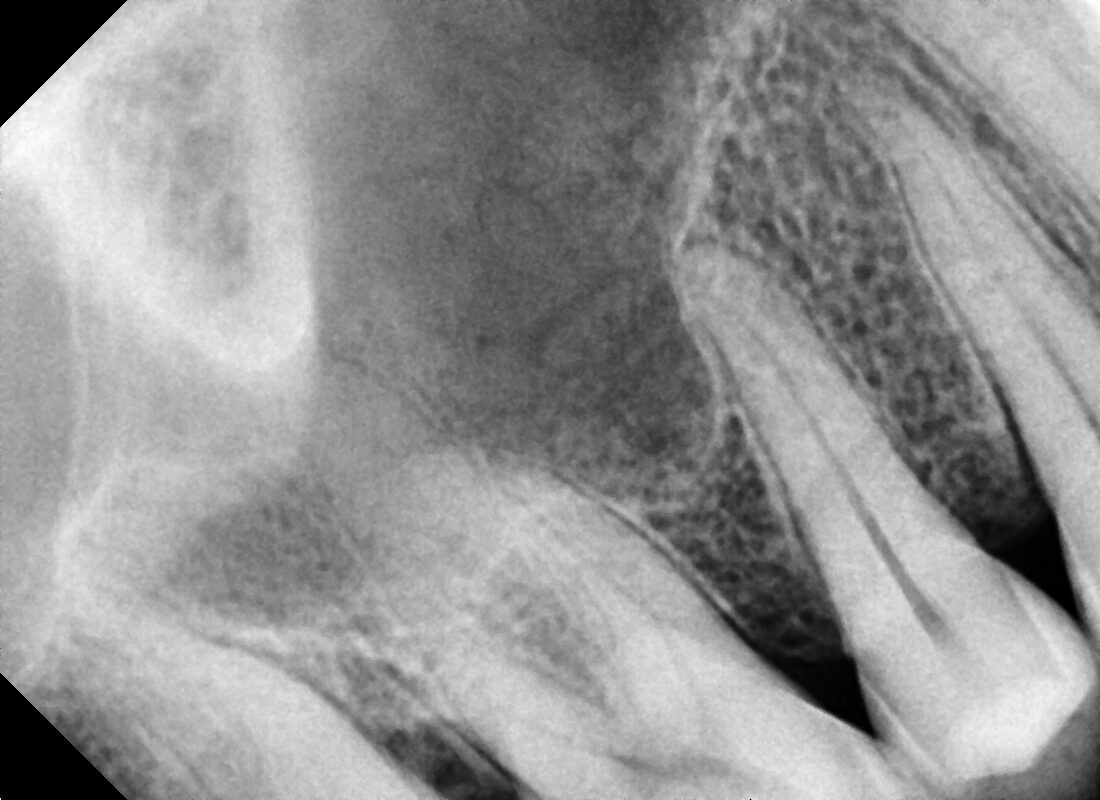

POST RADIOGRAPH